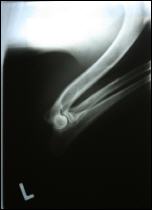

Allys linker Ellbogen gebeugt Allys rechter Ellbogen gebeugt